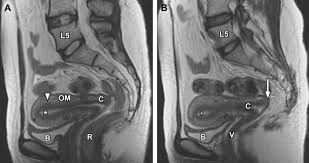

Above the pelvic brim and has no obstetric importance. Related online courses on physioplus. The pelvis (plural pelves or pelvises) is either the lower part of the trunk of the human body between the abdomen and the thighs (sometimes also called pelvic region of the trunk) or the skeleton embedded in it (sometimes also called bony pelvis, or pelvic skeleton). Pelvises or pelves) can refer to either the bony pelvis or the pelvic cavity. 3d interactive models and tutorials on the anatomy of the abdomen and pelvis. Journal of anatomy and physiology, vol. There are many organs that sit in the pelvis, including much of the urinary system, and lots of the male or female reproductive systems. Surgical pelvic anatomy in gynecologic oncology. This mri pelvis cross sectional anatomy tool is absolutely free to use. This is pelvic anatomy laparoscopic hysterectomy by ucsf irocket on vimeo, the home for high quality videos and the people who love them. Laparoscopic anatomy of the female pelvic region. I've been putting this together for a while and am very excited to share this with you! Pelvic floor anatomy & function:

This mri pelvis cross sectional anatomy tool is absolutely free to use. It is composed of inlet, cavity, and outlet. Functional anatomy of the male pelvic floor online course: Structure of the bony pelvis, pelvic floor insufficiency, inguinal region and hernia. The pelvis (plural pelves or pelvises) is either the lower part of the trunk of the human body between the abdomen and the thighs (sometimes also called pelvic region of the trunk) or the skeleton embedded in it (sometimes also called bony pelvis, or pelvic skeleton).